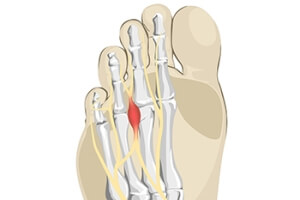

Treatment of Morton’s Neuroma

Morton’s Neuroma

Morton's neuroma is a painful foot condition that commonly affects the areas between the second and third or third and fourth toe, although other areas of the foot are also susceptible. Morton’s neuroma is caused by an inflamed nerve in the foot that is being squeezed and aggravated by surrounding bones.

What is Morton's Neuroma?

Morton’s neuroma, (also referred to as Morton’s metatarsalgia, Morton’s neuralgia, plantar neuroma or intermetatarsal neuroma) is a condition that is caused when the tissue around one of the nerves between your toes begins to thicken. This thickening can result in pain in the ball of the foot. Fortunately, the condition itself is not cancerous.

Morton’s neuroma affects women more often than men with a ratio of 4:1. It tends to target women between the age of 50 and 60, but it can occur in people of all ages. There are some risk factors that may put you at a slightly higher risk of developing the condition. People who often wear narrow or high-heeled shoes are often found to be linked to Morton’s neuroma. Additionally, activities such as running or jogging can put an enormous amount of pressure on the ligament and cause the nerve to thicken.

There usually aren’t any outward symptoms of this condition. A person who has Morton’s neuroma may feel as if they are standing on a pebble in their shoe. They may also feel a tingling or numbness in the toes as well as a burning pain in the ball of their foot that may radiate to their toes.

In order to properly diagnose you, the doctor will press on your foot to feel for a mass or tender spot. He may also do a series of tests such as x-rays, an ultrasound, or an MRI. X-rays are usually done to rule out any other causes for your foot pain such as a stress fracture. Ultrasounds are used to reveal soft tissue abnormalities that may exist, such as neuromas. Your podiatrist may want to use an MRI in order to visualize your soft tissues.

There are three main options for treatment of Morton’s neuroma: Injections, decompression surgery, and removal of the nerve. Injections of steroids into the painful area have been proven to help those with Morton’s neuroma. Decompression surgery has been shown to relieve pressure on the affected nerve by cutting nearby structures such as the ligaments in the foot. Another treatment option would be to surgically remove the growth to provide pain relief.